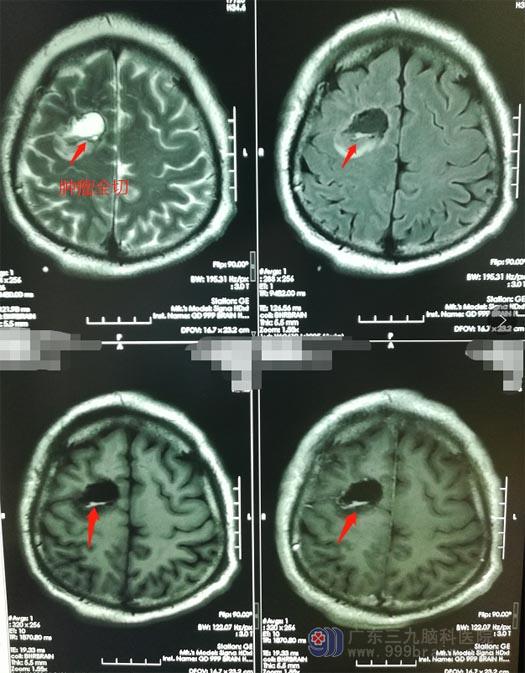

5天后,正在散步的钟叔再次出现突然晕厥,不仅如此,同时还伴有四肢抽搐、口吐白沫,和之前一样,几分钟后醒来的钟叔和正常人一模一样。家人慌了,虽然只是短短的几分钟时间,这要是发生在马路上、楼梯上、水塘边,后果真是不堪设想。意识到问题严重性的家人带着钟叔到当地医院就诊,影像检查发现颅内出现了肿瘤。

在广东三九脑科医院进一步检查后,钟叔被诊断为:右侧额叶占位病变、症状性癫痫。

充分的术前准备后,鲁明带领团队为钟叔行“唤醒麻醉下右侧额叶病变切除术”,术中,利用电生理及唤醒麻醉技术,在显微镜下避开脑功能区,完整地切除了肿瘤。